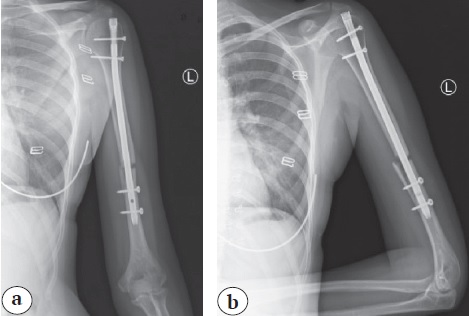

Выполнено удаление штифта. Отломки выделены из рубцовых тканей, освежены, сопоставлены и фиксированы экстраартикулярной пластиной с угловой стабильностью с созданием компрессии (рис. 4).

Рис. 4. Рентгенограммы после реостеосинтеза левой плечевой кости пластиной; положение отломков и металлофиксатора удовлетворительное: a — прямая проекция; b — боковая проекция

Fig. 4. X-rays after re-fixation of the left humeral bone with a plate; the position of the fragments and metal fixator is satisfactory: a — anteroposterior view; b — lateral view